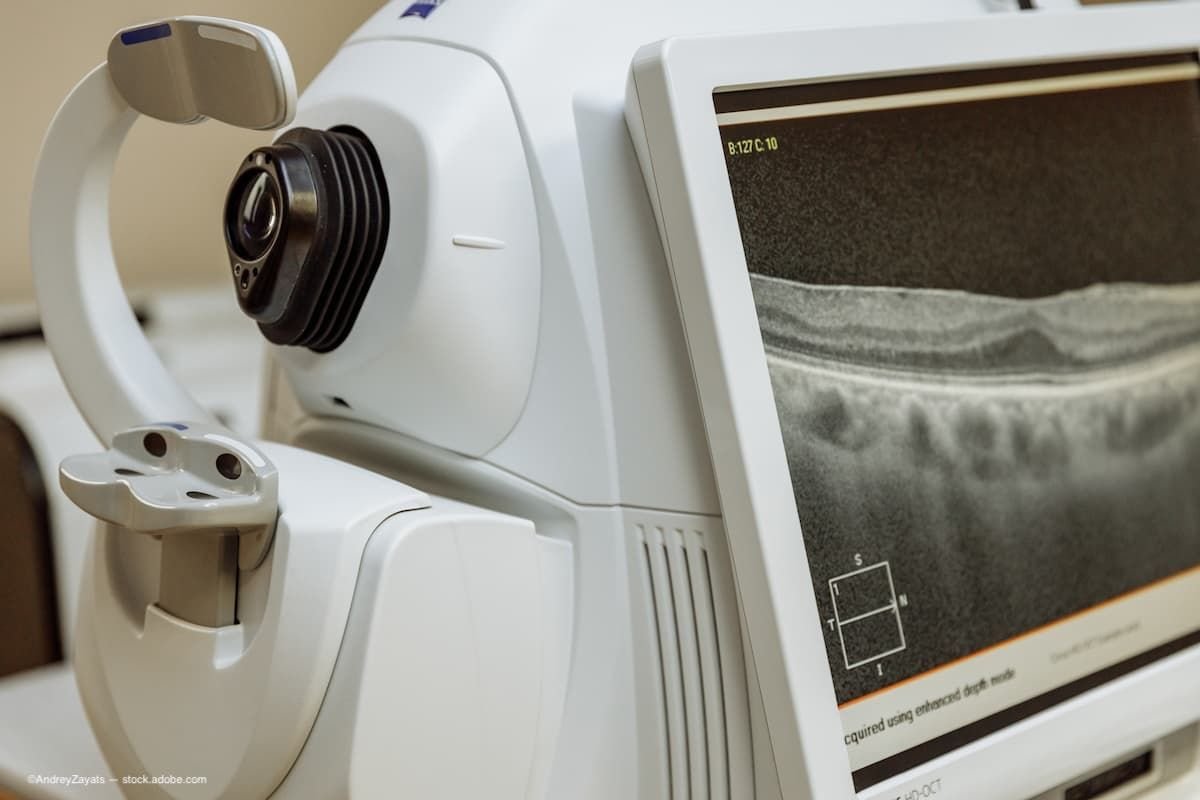

A recent conference celebrated the creation of the first prototype of the spectral optical coherence tomography (SOCT) instrument. Introduced in 2000, the prototype, which was developed at the Institute of Physics of Nicolaus Copernicus University in Toruń, Poland, was the basis for the world’s first commercial SOCT device introduced in 2004, according to a press release issued by the OFTALMIKA Eye Clinic, Bydgoszcz, Poland.

“Often compared to ‘optical histology,’ OCT provides highly detailed images of the retina, cornea, and optic nerve. It enables early detection and monitoring of glaucoma, age-related macular degeneration, diabetic retinopathy, and many other eye conditions,” the press release related. Adding to that, Professor Jakub Kaluzny emphasized, “OCT has become the global gold standard in ophthalmology diagnostics, transforming how we care for vision health.”